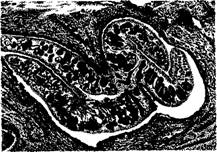

Фасциолез печени. Расширенные желчные протоки с утолщенными стенками

Гистологически в просвете желчных протоков и разветвленной воротной вены можно обнаружить эмболирующих сосуды молодых фасциол, лежащих среди эритроцитов и лейкоцитов, а также разрушение печеночных клеток, гемосидероз, разрастание юных соединительнотканных клеток. При хроническом течении на месте этих повреждений образуются очаги рубцовой ткани. На месте поселения фасциол в желчных ходах развивается вначале катаральный холангит, а затем билиарный цирроз. Печень увеличена, бугристая, плотной консистенции, неравномерно окрашена в зеленовато-коричневый цвет. Снаружи и на разрезе видны толстые (до 2тАФ3 см) извилистые желто-белые тяжи расширенных желчных протоков. Стенки их утолщены (до 3тАФ5 мм), хрящеподобной консистенции, содержат полужидкую зеленовато-коричневую массу с половозрелыми фасциолами, количество которых достигает нескольких десятков и сотен экземпляров. В брюшной полости скопление транссудата. В кишечнике острый катаральный энтерит, каловые массы жидкой консистенции, слабо окрашены желчью. Паренхиматозные органы в состоянии зернистой дистрофии. В подкожной, межмышечной тканях отек, атрофия жировой клетчатки (истощение), желтуха.

Фасциолез. Тела паразитов в просвете небольшого желчного протока